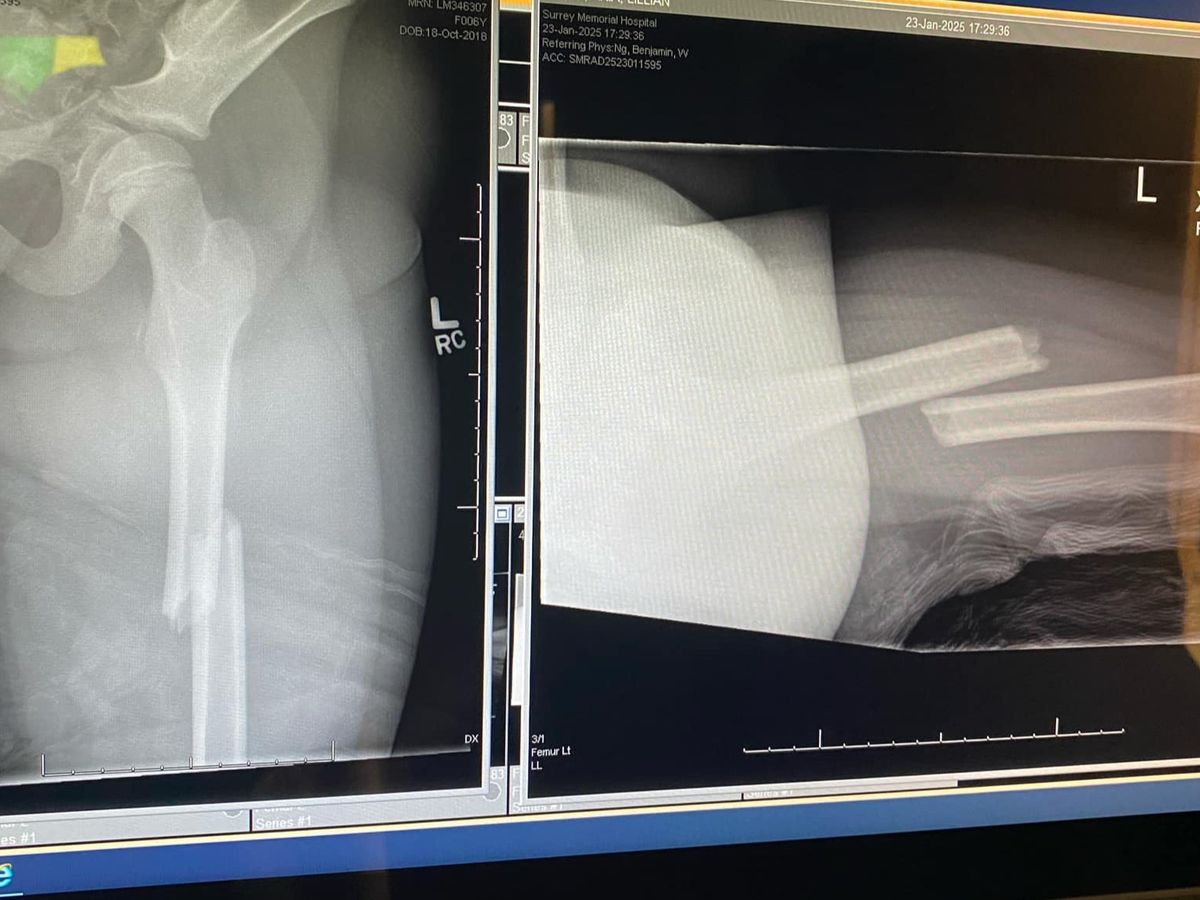

She fell 12+ feet off the top of the playground and snapped her femur right in half. She has a very long road of recovery ahead of her, that includes multiple surgeries, trips to children’s hospital, and simply being wheelchair bound.